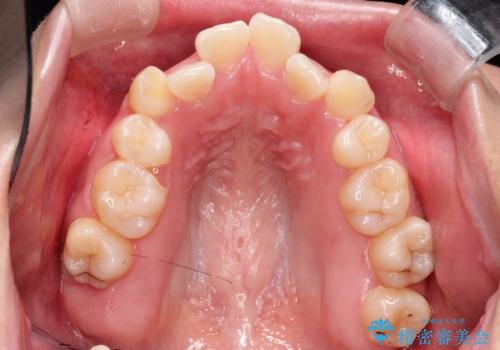

- 前歯のでこぼこが気になると来院されました。

奥歯の噛み合わせは綺麗に噛んでいたため、前歯の叢生(でこぼこ)を、短期間で治療完了するように計画しました。